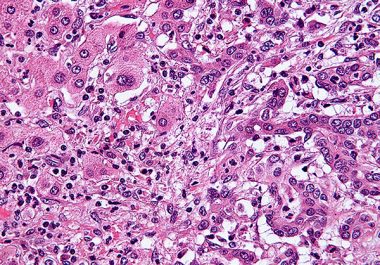

The FDA approved a combination of an immunotherapy and a therapeutic that can stop tumors from growing blood vessels for certain patients with liver cancer.

The FDA approved using a combination of nivolumab and ipilimumab, two immune checkpoint inhibitors, to treat certain patients with hepatocellular carcinoma.

The FDA expanded the use of the immunotherapy pembrolizumab to include the treatment of certain patients with liver cancer.